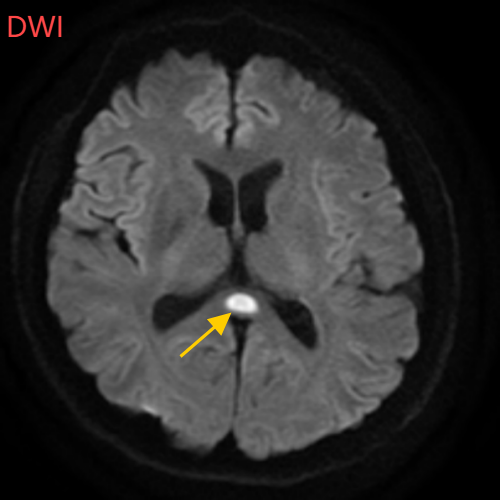

医生摇摇头,经过头部磁共振平扫、弥散、增强影像等检查,医生诊断,小董是得了一种比较少见的病症:可逆性胼胝体压部综合征。

小董的影像结果显示,胼胝体压部发生病变